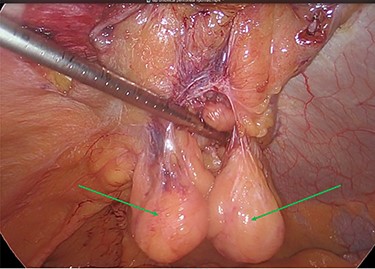

The viable omentum was reduced into the peritoneal cavity. Two lipomas were then observed attached to the parietal peritoneum (Figs 3 and 4). The lipomas were also reduced into the peritoneal cavity from within the hernia sac. Each one was 2 cm in diameter based on laparoscopic visualization using the 1 cm markings on a suction irrigation device.

The two peritoneal lipomas (green arrows) and the visible umbilical hernia neck (blue circle). Intracorporeal suturing of the hernia neck (green arrow) and closure of the hernial defect.

The decision was taken intraoperatively to leave the lipomas in situ as the hernia neck had been repaired, and it was thought that they could no longer cause any issue with pain or possible hernial reincarceration (Fig. 7).

Mesh reperitonealization and parietal peritoneal lipomas in situ (green arrows).